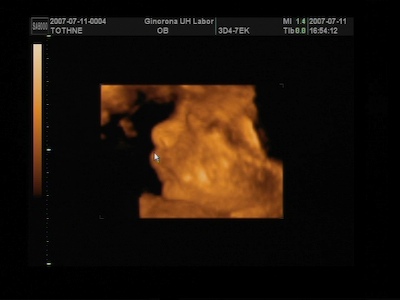

A 4D-s vizsgálaton nekem azt mondták ,hogy 5 nappal kisebb a baba, de ez még belefér ezért nem változtattak semmin , és lehet,hogy még előbb is kibújhat.